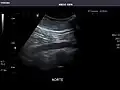

Abdominal Ultrasound (Full Exam)

STRUCTURED REPORT

(Technique: Transabdominal ultrasonography; Device: Toshiba Aplio XG)

Aorta: Visualized portions normal in caliber, 16 x 15 mm.

IVC: Normal.

IMPRESSION:

Normal abdominal ultrasound.

Aorta -